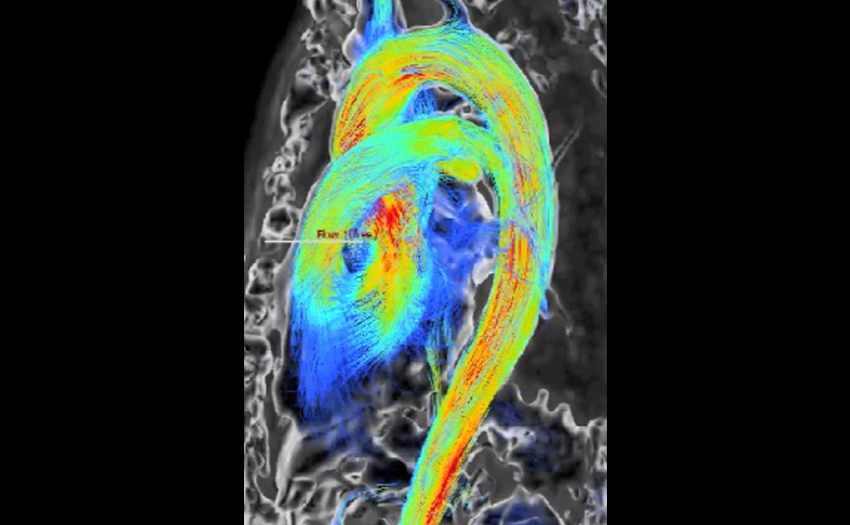

- Cardiac CT: Full Cardiac and Cardiovascular CT training on 256 slice GE Revolution scanner. Including Coronary CTA, Vascular CTA and preoperative structural CT imaging for transcatheter intervention planning.

- Cardiac MRI: Additional training possible in Cardiac MRI in collaboration with both the Cardiology and Radiology departments.